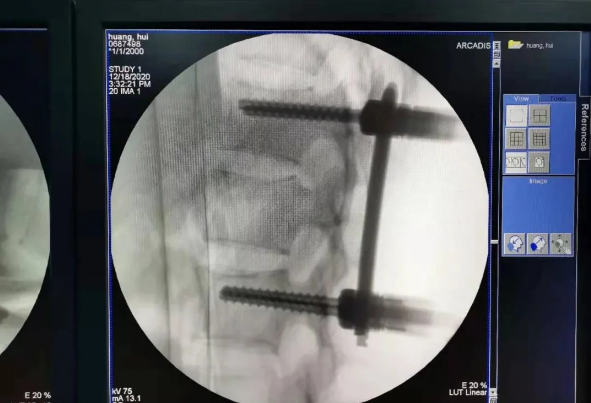

在南昌市第一医院廖琦教授向导下,由创伤骨科团队借助天玑?骨科手术机械人为患者“量身定做”最理想、最清静的教科书般的通道,完善清静微创完成手术,并且手术时间显着缩短,真正做到“指哪儿打哪儿”!更让患者定心的是,天玑?骨科手术机械人的“稳固手”机械臂举行精准定位,不必重复探寻。

由于天玑?骨科手术机械人的精准及高效,可以使手术时间显着缩短,因此在骨盆骨折手术后,在廖琦教授指导下,脊柱外科团队使用天玑?骨科手术机械人同样为20岁女性腰椎骨折患者“量身定做”最理想、最清静的教科书般的通道,完善清静微创完成手术,手术不但时间缩短,并且出血和透视镌汰。

天玑?骨科手术机械人系统由机械臂主机、光学跟踪系统、主控台车组成,“透视眼”、“稳固手”是它的厉害之处,因此一举解决了骨科手术有三浩劫题:视野差、精准难、不稳固。

? 机械臂就是天玑?骨科手术机械人的“稳固手”,运动无邪、操作稳固,能抵达亚毫米的精度;